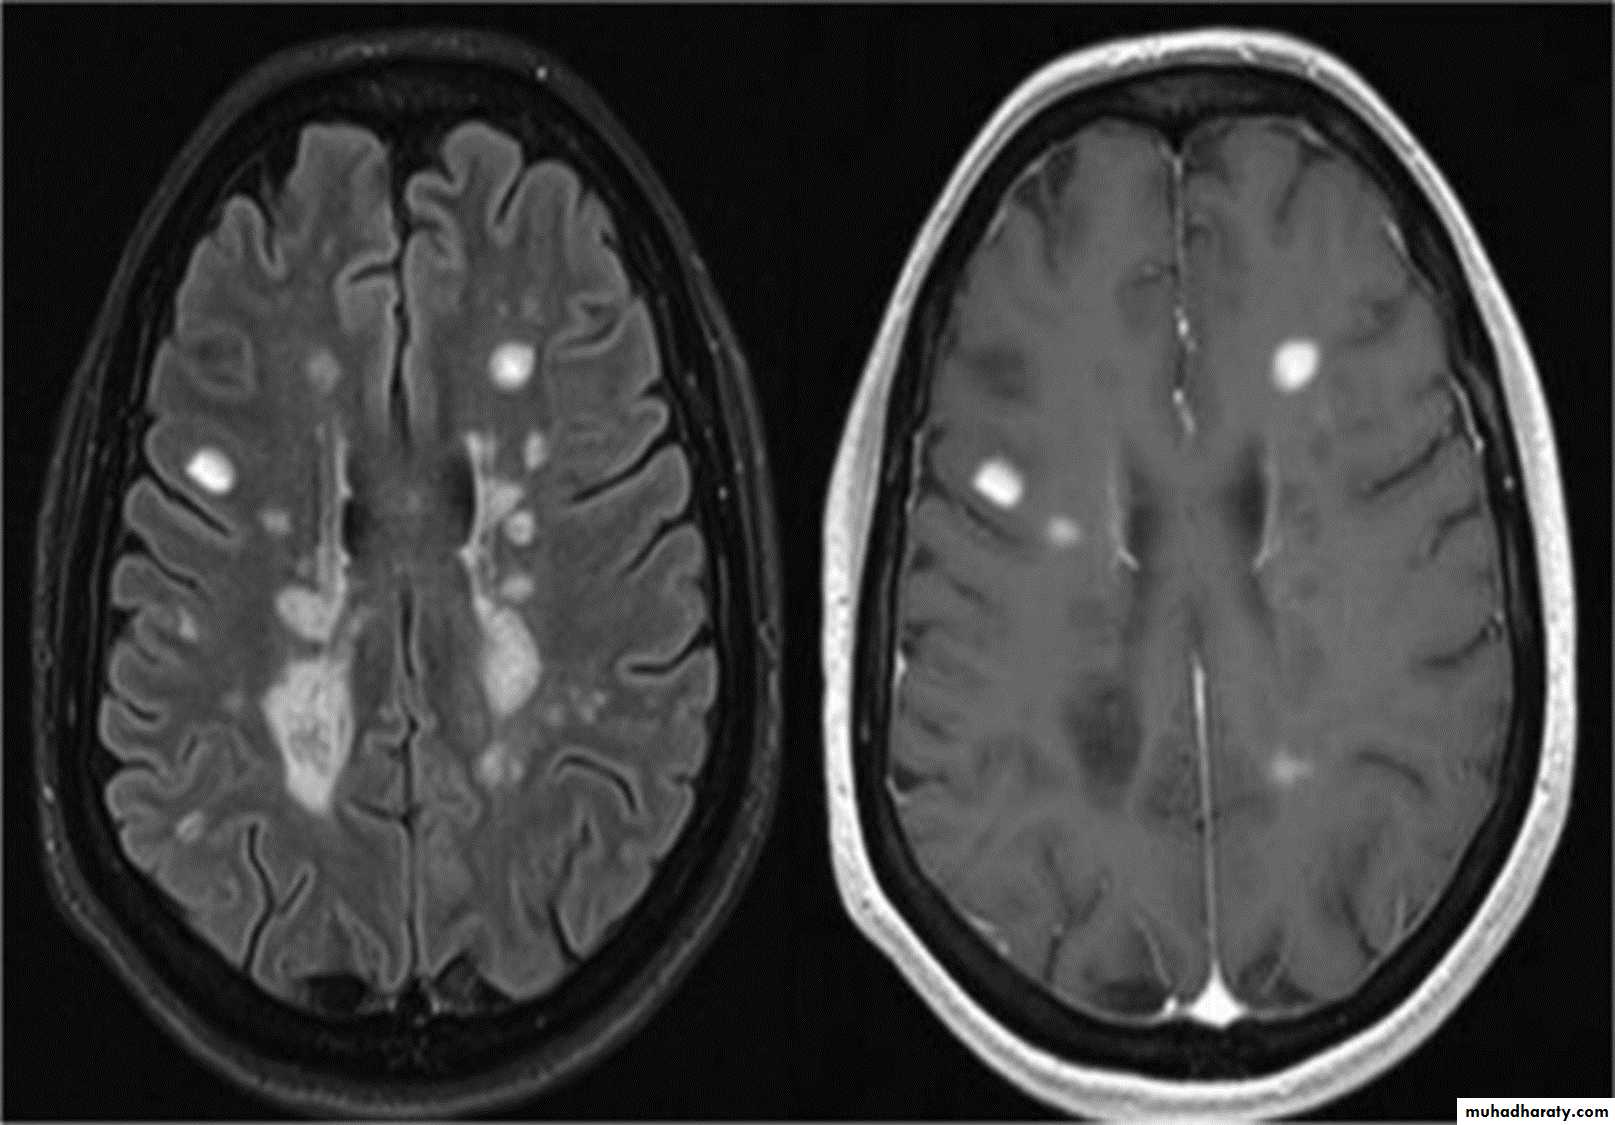

MRI :characteristic abnormalities are found in >95% of patients, although more than 90% of the lesions visualized by MRI are asymptomatic

Lesions are frequently oriented perpendicular to the ventricular surface,(Dawson’s fingers)

Lesions larger than 6 mm located in the corpus callosum, periventricular white matter, brainstem, cerebellum, or spinal cord are particularly helpful diagnostically